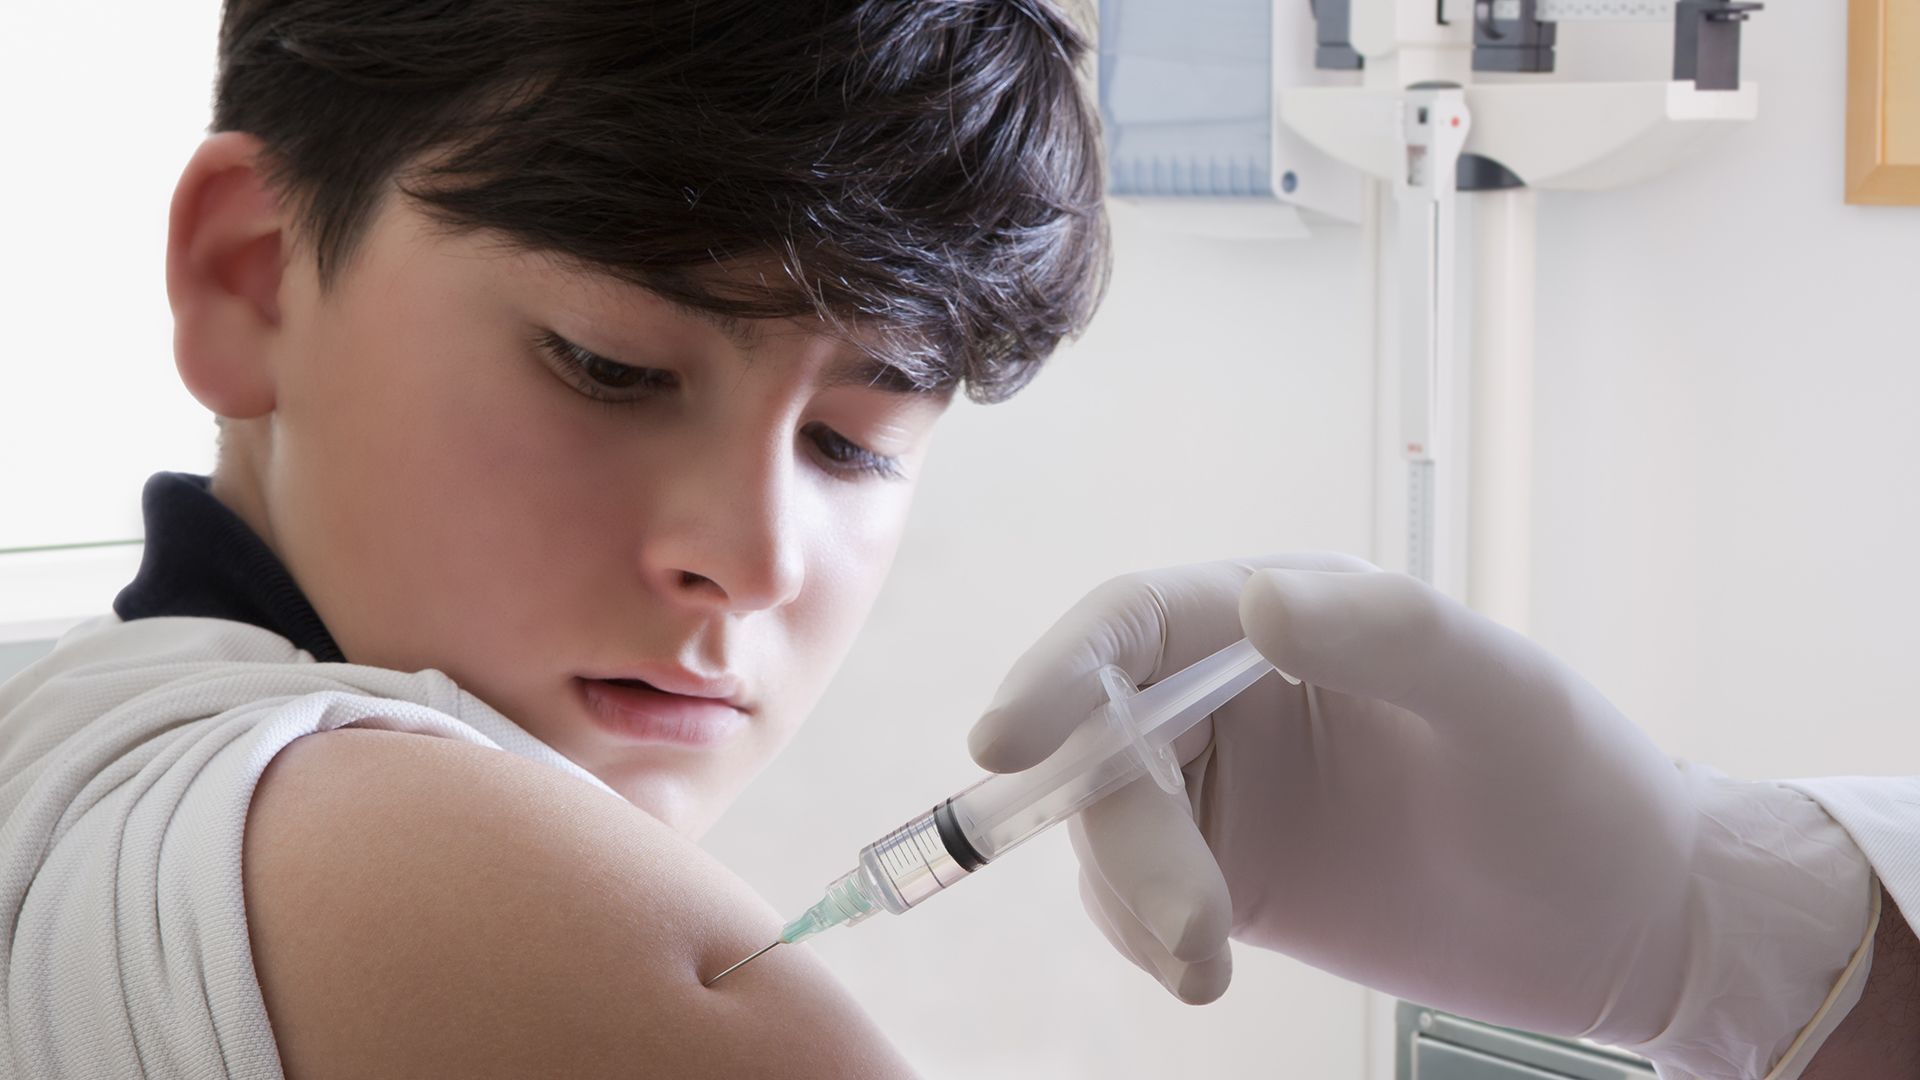

Nincs bizonyíték a BCG-oltás koronavírussal szembeni hatására

Egy gyermek halálát okozta a tbc elleni védőoltás Ukrajnában

Védőoltás fertőzött meg egy 20 hónapos babát – az életéért küzdenek